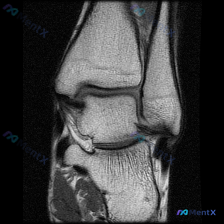

刚看到一个很有代表性的读片病例,临床怀疑膝关节软骨异常,给了单幅膝关节矢状位T2加权MRI,整理一下分析思路分享给大家。 病例基本信息 - 临床问题:标识图像显示的异常是否为软骨异常 - 影像资料:单幅膝关节矢状位T2加权(或脂肪抑制质子密度加权)MRI,图像质量好,无运动伪影,覆盖股骨远端、胫骨近...